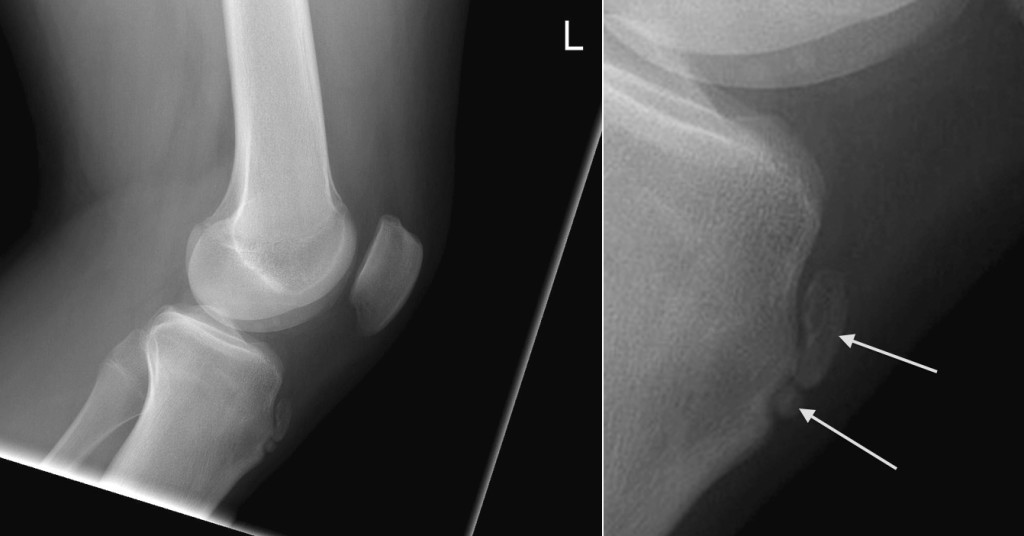

From www.wikiradiography.net

OsgoodSchlatter Disease wikiRadiography What Is The Difference Between Osgood Schlatter S And Patellar Tendonitis It is an inflammation of the area just below the knee where the tendon from the kneecap (patellar. Osgood schlatter disease, also known as osteochondrosis or traction apophysitis of the tibial tubercle, is a common cause of. The tibial tubercle (the tuberosity of the tibia) is the protuberance along the anterior aspect of the tibia, just distal to the anterior. What Is The Difference Between Osgood Schlatter S And Patellar Tendonitis.